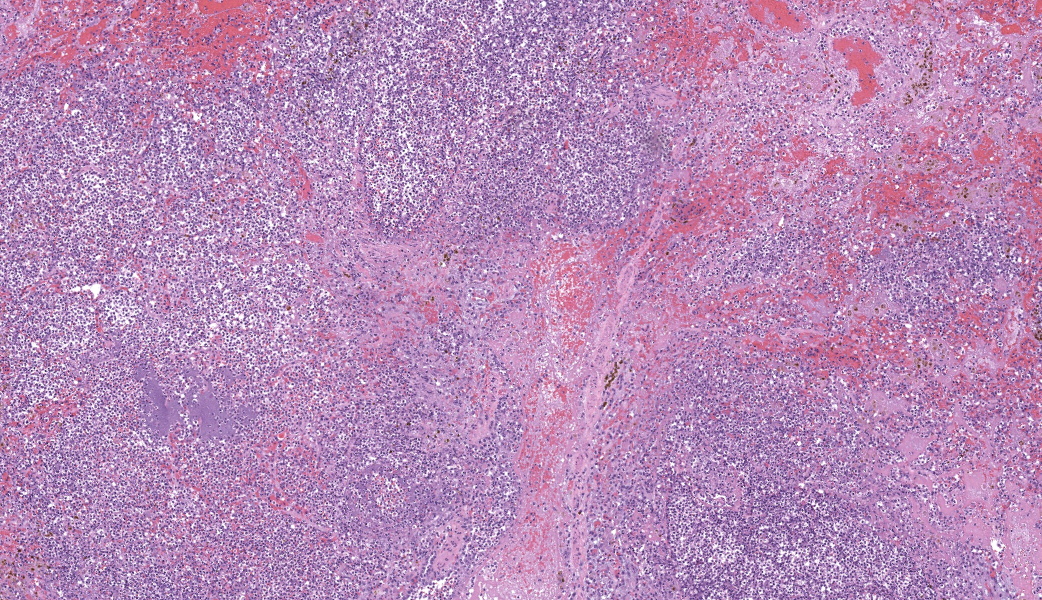

Regionally, sharply demarcated areas of the pulmonary parenchyma are markedly necrotic and replaced by abundant hemorrhage, fibrin, inflammatory infiltrates composed mainly of neutrophils and macrophages, and necrotic cellular debris. In these areas, multiple blood vessels contain thrombi consisting of large numbers of degenerate neutrophils, organizing fibrin, occasional colonies of bacterial coccobacilli, and necrotic cellular debris that variably obscure the lumen and vessel walls. Affected vessels often have smudgy, hypereosinophilic walls that are transmurally infiltrated by neutrophils, lymphocytes, and macrophages. In less affected regions, the alveolar spaces contain a small amount of fibrin, numerous foamy alveolar macrophages (some of which contain brown granular hemosiderin pigment), and fewer neutrophils and erythrocytes. There are moderate numbers of hemosiderin-laden macrophages mostly concentrated around pulmonary arteries, multifocally. Regionally, along the pleural surface there is a large amount of fibrin admixed with numerous degenerate neutrophils and necrotic cellular debris. The pleura itself is mildly thickened by fibrous connective tissue and edema and is multifocally lined by markedly reactive mesothelium, characterized by plump, rounded mesothelial cells.

Heart, right atrioventricular valve: Marked, chronic, fibrinosuppurative valvular endocarditis with intralesional bacterial colonies; Mild, multifocal, suppurative epicarditisLungs: Marked, regional, suppurative, necrotizing embolic pneumonia with vascular thrombosis and intrathrombotic bacteria; Marked, regional, fibrinosuppurative pleuritis

2. Lung: Pneumonia, embolic, necrotizing and suppurative, chronic, multifocal to coalescing, severe, with septic arterial thrombi and suppurative pleuritis.